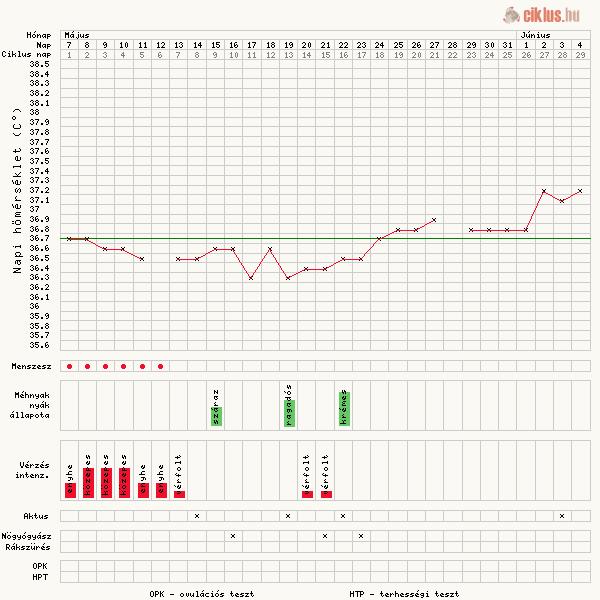

A hom továbbra is tartja a 36,8 -at. Se fel, se le. De már érzem, hogy fájdogál a hasam. Remélem nem a mensit jezi. Tegnap este érzetem egy kis hányingert, de már nem tulajdonítok neki jelentoséget, mert az elmúlt hónapokban is így éreztem.

Orulok, hogy a doki mindent redben talált. A táblázatból kivehetnéd a májusi programot, és helyette mehet június 11-e tesztelés. Akkor lesz a 20. DPO, feltéve ha eljutok odáig

Jobbulást kívánok. Nagyon szépen alakul a gorbéd, jó magasan van, akárcsak Krisztinkának. Nekem most valahogy nem akar feljebb menni.

Ciklus.hu-n is lehet hogorbét csinálni. Az sem roszz, nézd meg.